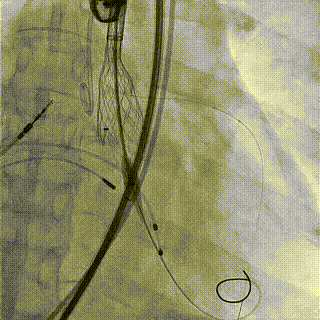

术中影像

1.主动脉根部造影,可见大量反流

2.输送系统过主动脉弓

3.输送系统造影定位

4.释放瓣膜

5.瓣膜完全释放

6.最终造影,反流消失

手术结果

术后食道超声及造影未见瓣周漏,效果良好,手术圆满完成。